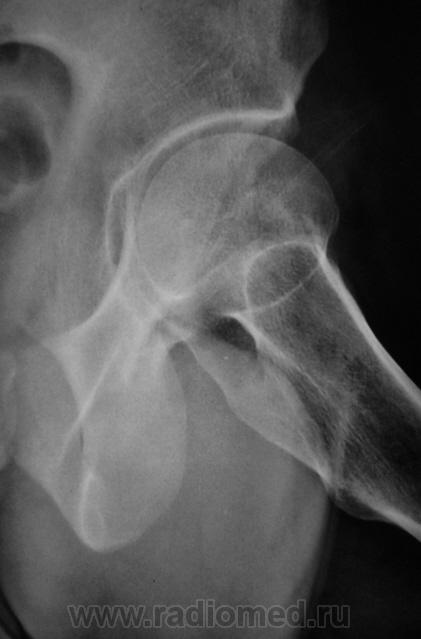

Наряду с очагом в головке, видится мне ещё и перелом - линейное нарушение кортикального слоя. И ещё очаг в крыле подвздошной кости (но может и придираюсь). Я бы взял изначально на МРТ таза и тазобедренных суставов.

С учётом того, что у нас в ЦРБ нет "высоких лучевых технологий", мы ограничились "линейкой".

1.pc160007.jpg2.pc160008.jpg3.pc160009.jpg4.pc160010.jpg5.pc160011.jpg6.pc160012.jpg7.pc160013.jpg

Тут умеренная грибовидная чуть шейка укорочена...М-ть укладка сдрейфила и носками наружу уложили? никаких деструкций не вижу А в подвздошной кости газики ну итрохантер хорош